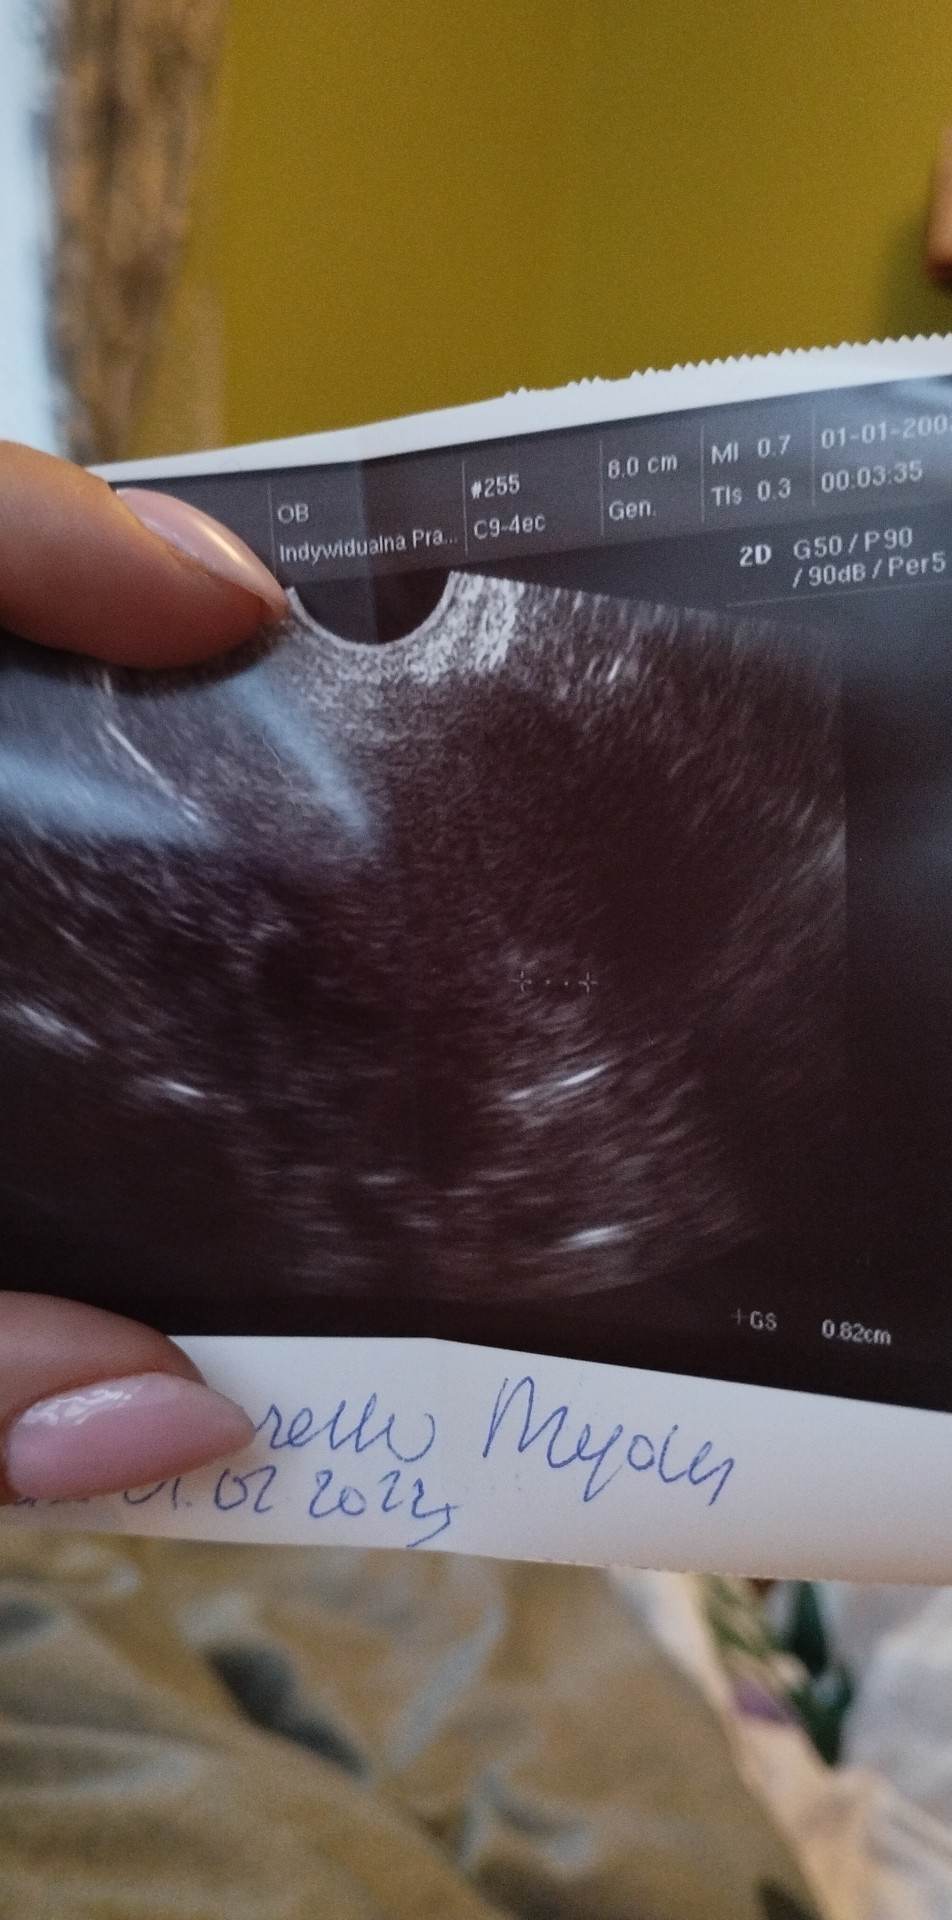

Cześć kochane. Ostatnią miesiączkę miałam 1 lutego, wczoraj byłam u ginekologa i widać mały pęcherzyk ciążowy, lekarz kazał brać kwas foliowy i przyjść 23 marca na wizytę. Według aplikacji termin na 8.11 :)

W nocy trafiłam z niewielkim plamieniem do szpitala, kiedy badał mnie ginekolog, powiedział, że według USG ciąża jest młodsza, i wynosi 5 tyg i 2 dni, lub rozwija się nieprawidłowo. Rano mają mi pobrać krew i mocz do badań, oraz zrobić powtórne USG czy pęcherzyk się powiększa. Powiedział, że tak naprawdę za tydzień okaże się czy wszystko ok. Nie wiem co o tym myśleć 🤦